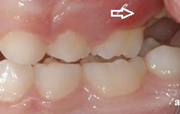

eesmine lahihambumus

lahihambumus, kui kontaktis on ainult molaarid ehk tagahambad

eeshambad ei ulatu kokku